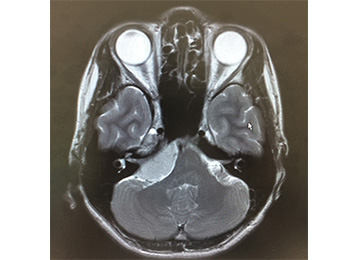

右小脳橋角部(右耳の奥)の腫瘍

脳を腫瘍が圧迫している